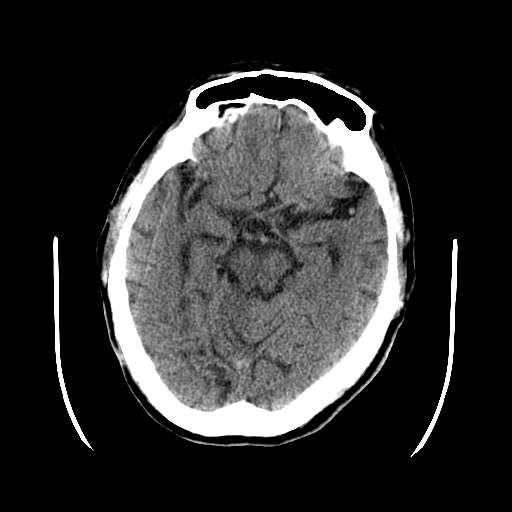

m 73

呕吐,意识障碍1小时,伴左侧偏瘫,自诉曾有过左眼视力下降。

病灶区ct值约75hu

考虑:1、中脑右侧、右侧小脑半球、双侧丘脑缺血性脑梗塞;

2、右侧后交通动脉动脉瘤;

3、双侧基底节区腔隙性脑软化灶;

4、脑白质稀疏症。